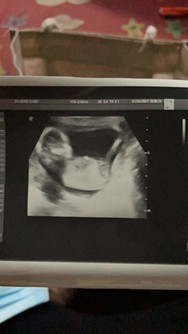

13week ชัดเหมือนกันจ้า

พึ่งซาวด์ตอน 14 week 6 day ค่ะ

เห็นเหมือนกันเลยจ้า